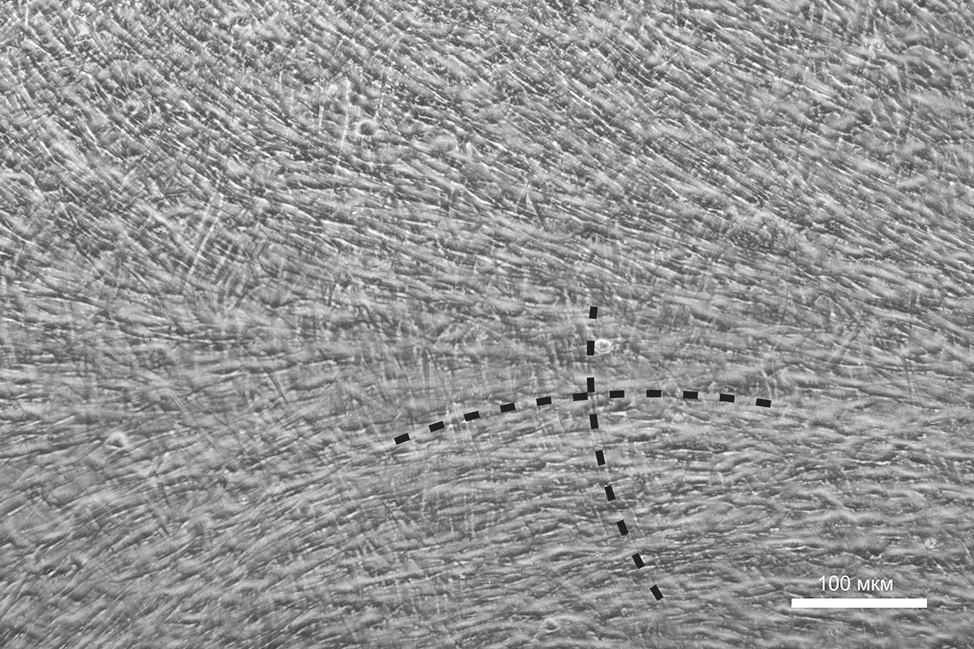

После засева в высокой плотности клетки на 2–3-й день организовывали взаимно-перпендикулярные ламели, морфологически сходные с организацией пластин коллагеновых волокон и кератоцитов в строме роговицы (рис. 1).

Fig. 1. The cell layer formed on the surface of the cell culture plastic plate on the fourth day of cultivation (phase-contrast microscopy). The dotted lines mark the keratocytes orthogonal orientation.